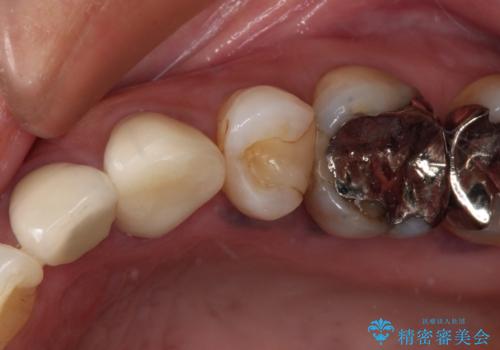

【根管治療】噛んだ時にしみる。最近になってズキズキ痛み、長引く痛みがある

担当医 河口智英